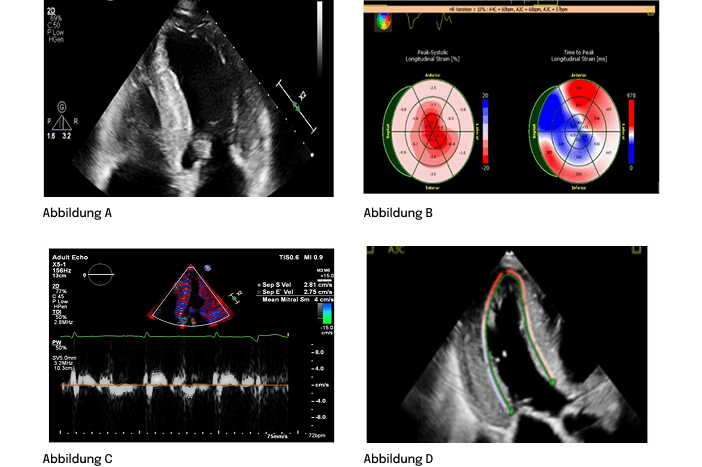

ECHO4

- hypertropher Phänotyp mit infiltrativen Merkmalen

- eingeschränkte LV-Füllung mit LV-Wandverdickung

- niedrige septale und laterale E-Welle

- Reduktion des globalen longitudinalen Strain